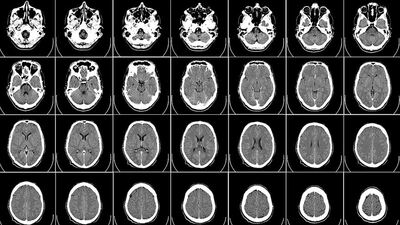

Newatlas sitesinin haberine göre, Cambridge Üniversitesinden bilim insanlarının, yaşları 9 ila 11 olan toplam 2 bin 700 çocuğun verilerini inceleyerek yaptıkları araştırmada, obez çocuklar ile normal kilodaki çocukların beyin yapılarında farklılıklar olduğu tespit edildi.

Çalışma çerçevesinde, obez çocukların beyinlerindeki prefrontal korteks bölgesinde incelme tespit edildiği, bu incelmenin de karar verme, kendini kontrol etme ve duyguların düzenlenmesi gibi davranışları olumsuz yönde etkilediği belirtildi.

Obezitenin beynin çalışma kapasitesine doğrudan etki yaptığını ortaya koyan çalışmada, obezite tedavisi gören ve kilo kaybeden kişilerin bilişsel kapasitelerinde gelişme gözlendiği de hatırlatıldı.

Uzmanlar, obezitenin mi beynin yapısına etki ettiğinin yoksa beyin yapısının mı obeziteyi tetiklediğinin gelecekte yapılacak araştırmalarla tespit edilebileceğinin altını çizdi.